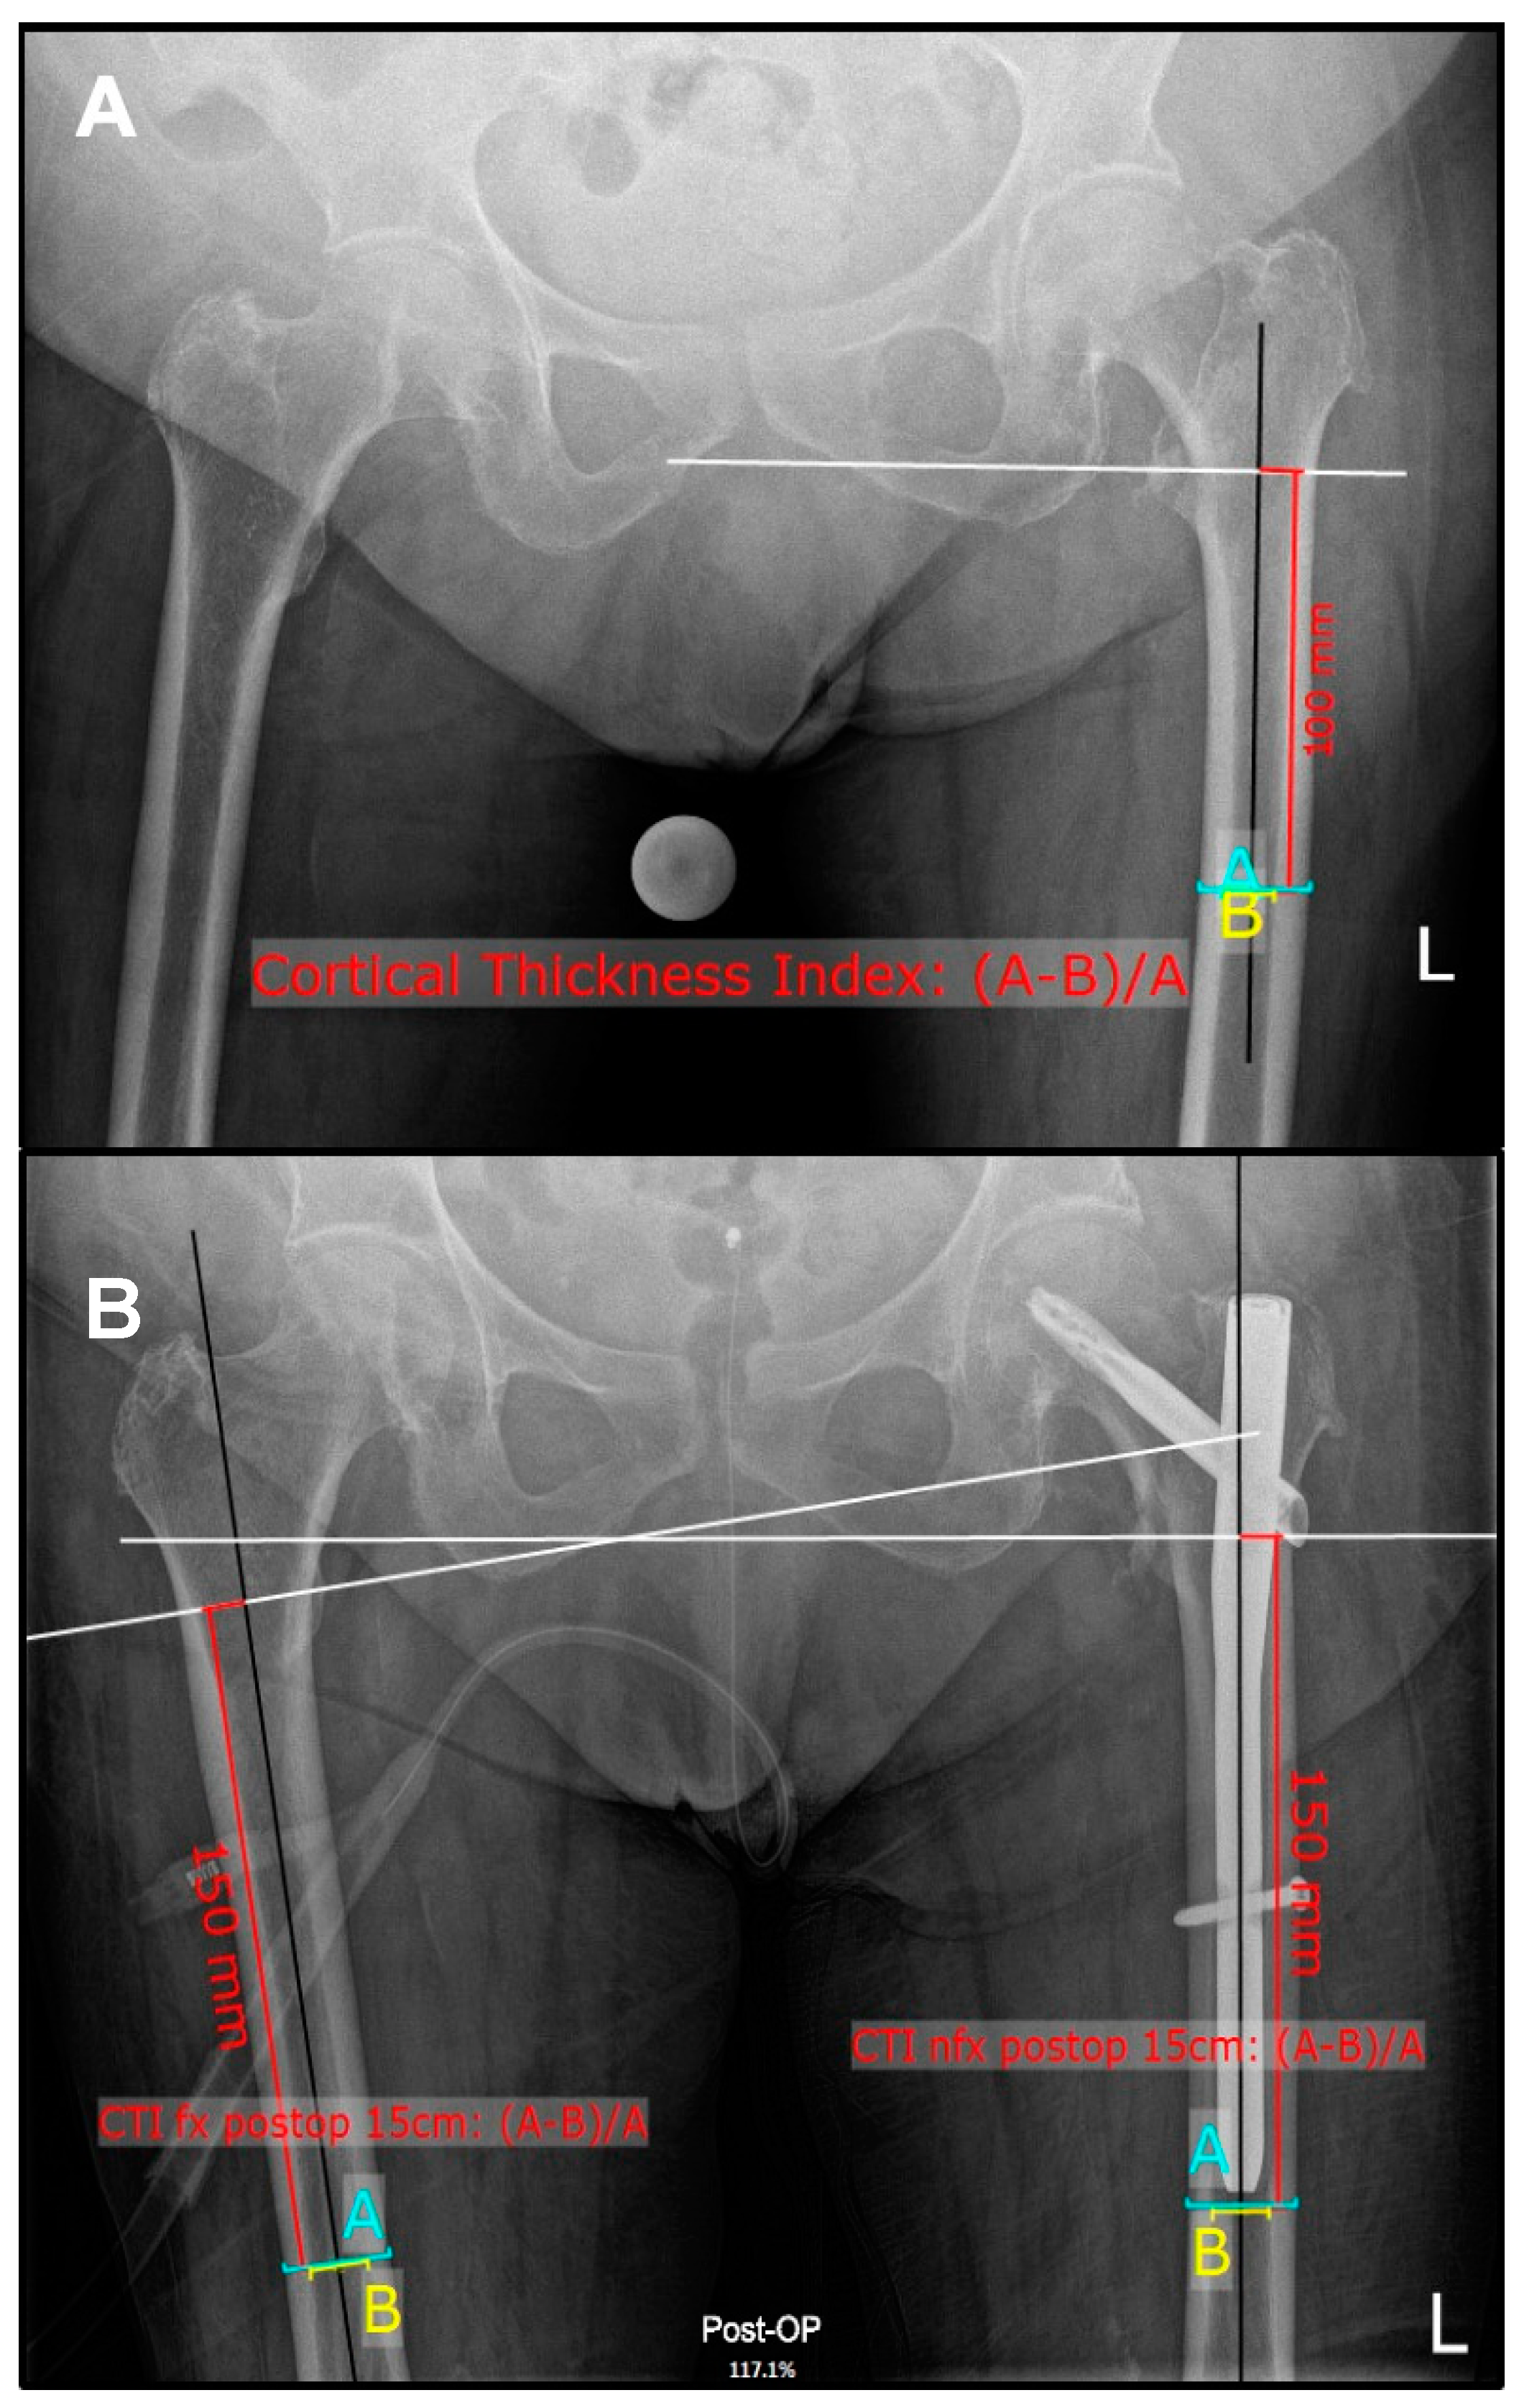

1. Introduction

2. Materials and Methods

2.1. Radiographic Measurements